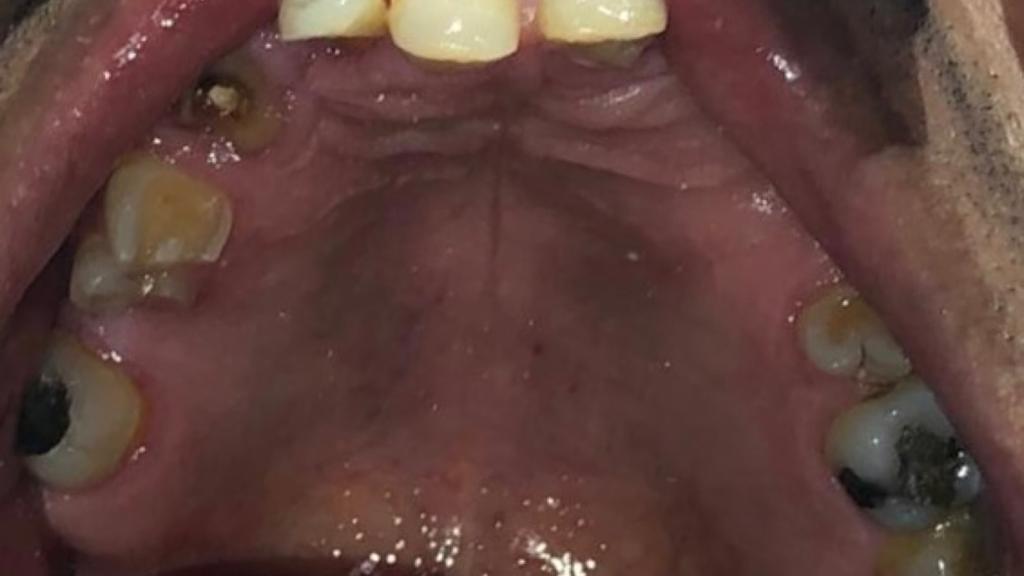

Fase 1: Diagnóstico inicial de rehabilitación oral

Fase 1

Rehabilitación Oral - Diagnóstico

Estado inicial del paciente con ausencia dental severa en maxilar inferior, afectando función masticatoria y estética.